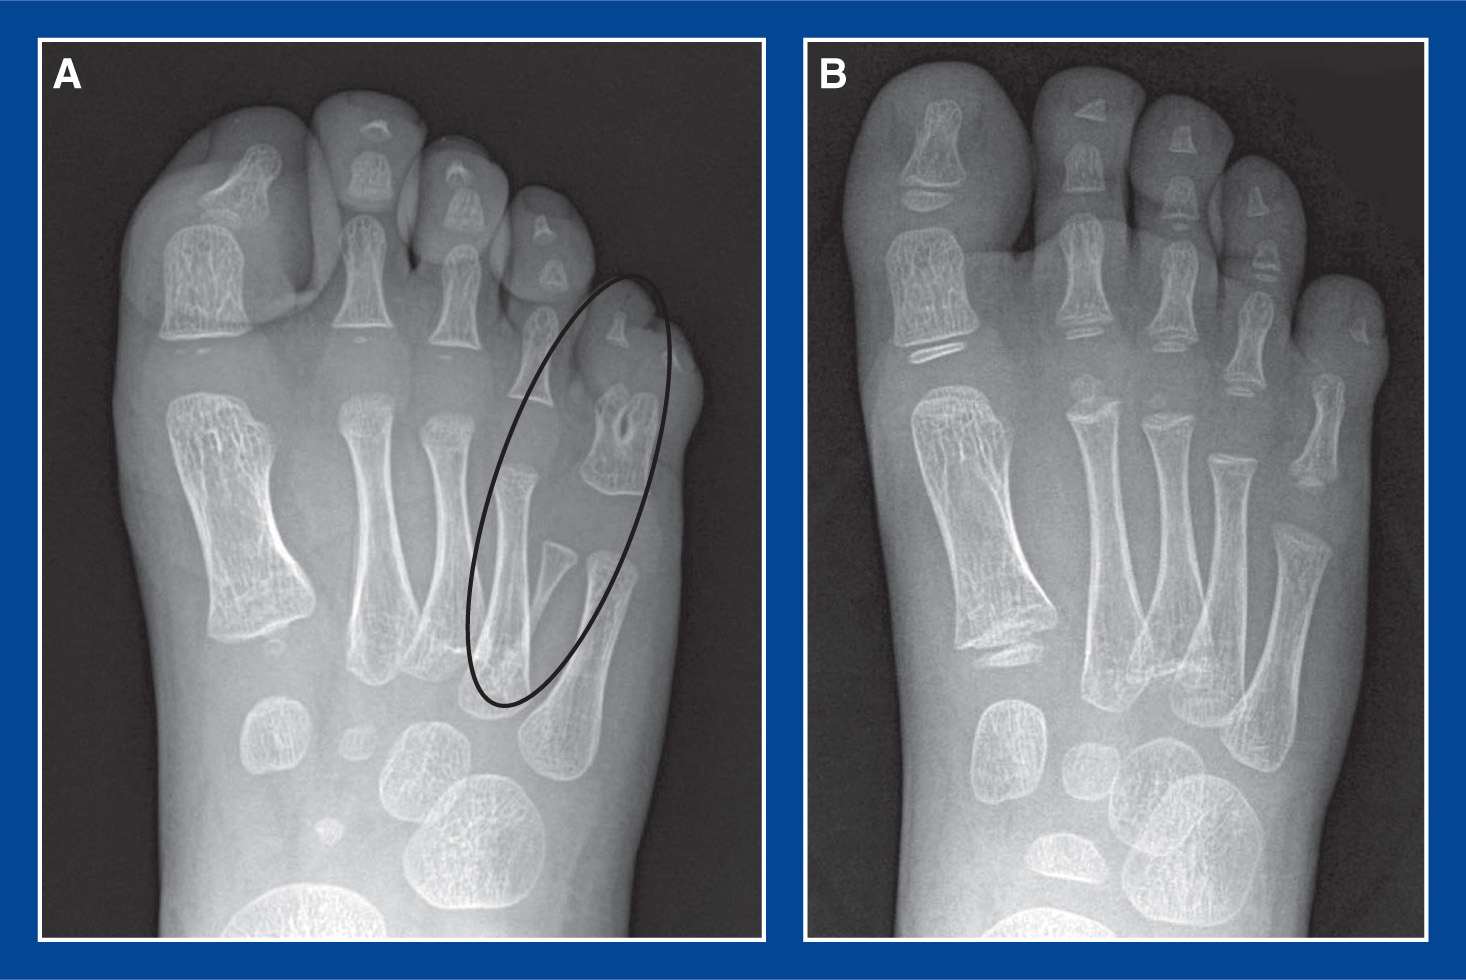

Figure 5 from Principles of management of growth plate fractures in the Toe Growth Plates If not treated properly, they can affect bone growth. Growth plate (physeal) fractures may be defined as disruptions in the cartilaginous physis of long bones that may or may not involve epiphyseal or. In growing children, sprains and strains often result in potentially serious growth plate fractures and physeal fractures (see the image below). Treatment is with closed reduction and. Toe Growth Plates.

Cureus Type 2 SalterHarris Physeal Injury of the Proximal Phalanx of Toe Growth Plates The growth plate is a section of cartilage children have at both ends of some bones, including. Open growth plates in children are often involved in fractures. A fracture of the growth plate is an injury to the soft tissue at the end of long bones in children and teens. Growth plate injuries are injuries to new bone tissue at. Toe Growth Plates.